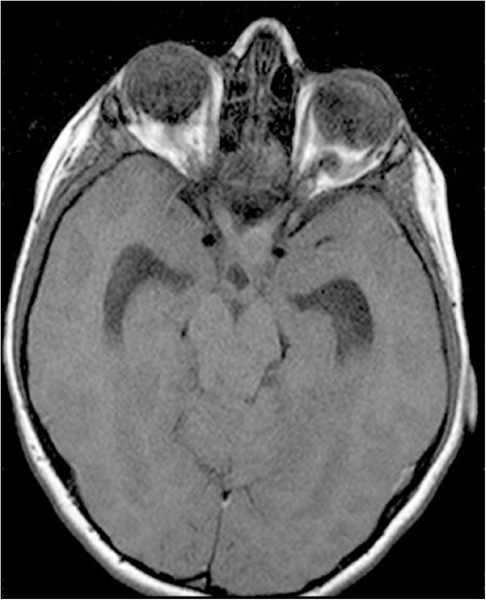

El craneofaringioma debe descartarse siempre en los casos de presunta pérdida visual psicógena y las ambliopías sin factores ambliogénicos como anisometropía o estrabismo, y atrofia óptica; por lo tanto está indicada una prueba de imagen. La tomografía computarizada (TC) muestra lesiones calcificadas quísticas en localización supraselar. Si el tumor es isodenso con el líquido cefaloraquídeo, puede únicamente aparecer distorsión de la cisterna supraselar. En la resonancia magnética (RM) los hallazgos dependerán de la composición del tumor: colesterol, metahemoglobina o malla trabecular ósea (Figura 2). Aunque histológicamente son tumores benignos, pueden tener un comportamiento agresivo por su localización y el diagnóstico diferencial se establece con el meningioma, el adenoma hipofisario, el disgerminoma, el quiste de la bolsa de Rathke y el quiste epidermoide supraselar.

Figura 2. Craneofaringioma RMN T2. Lesión de grandes dimensiones y redondeada con contenido líquido por el componente quístico de localización supraselar.